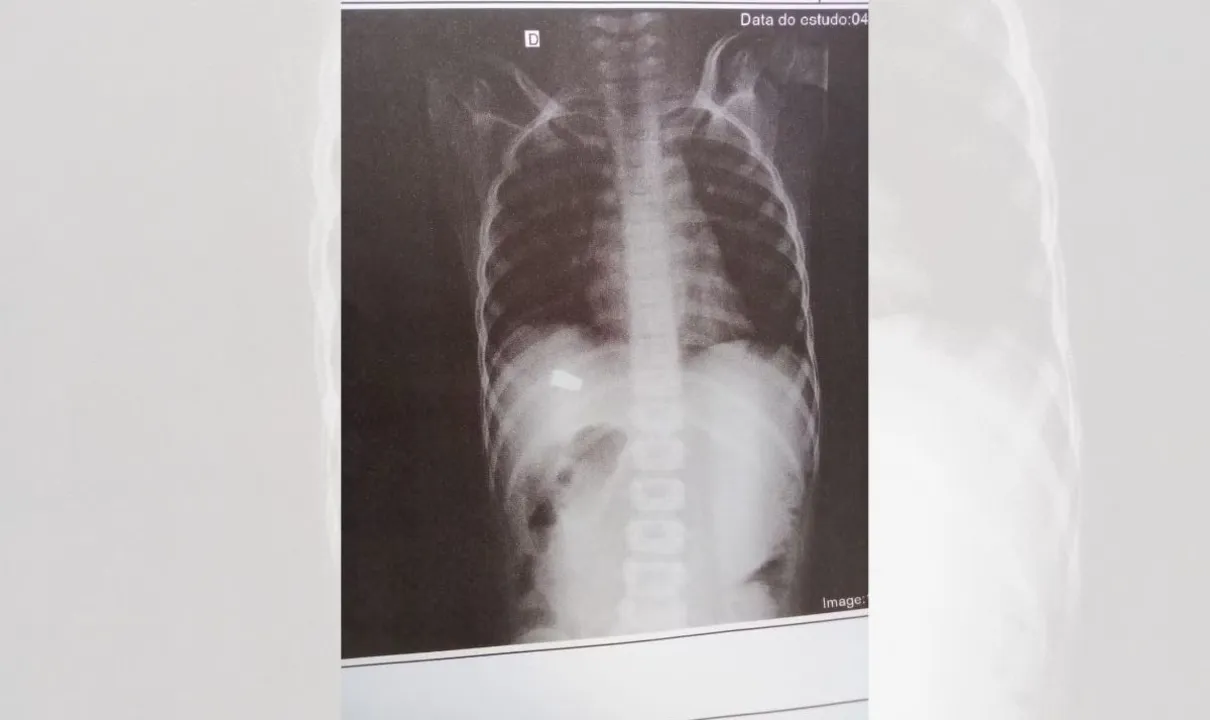

Inicialmente, a mulher levou o pequeno para Unidade de Pronto Atendimento (UPA) do bairro ao perceber que a criança tinha um sangramento. Ela não sabia no momento que se tratava de um tiro. Só na unidade de saúde, onde a criança fez um exame de raio-X, que os médicos descobriram que ela tinha sido atingida por um disparo.